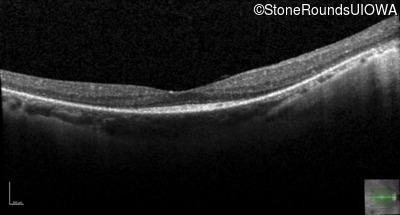

Optical Coherence Tomography - Left - 20/20 -2

Exemplar / OCT Stack

OCT Stack